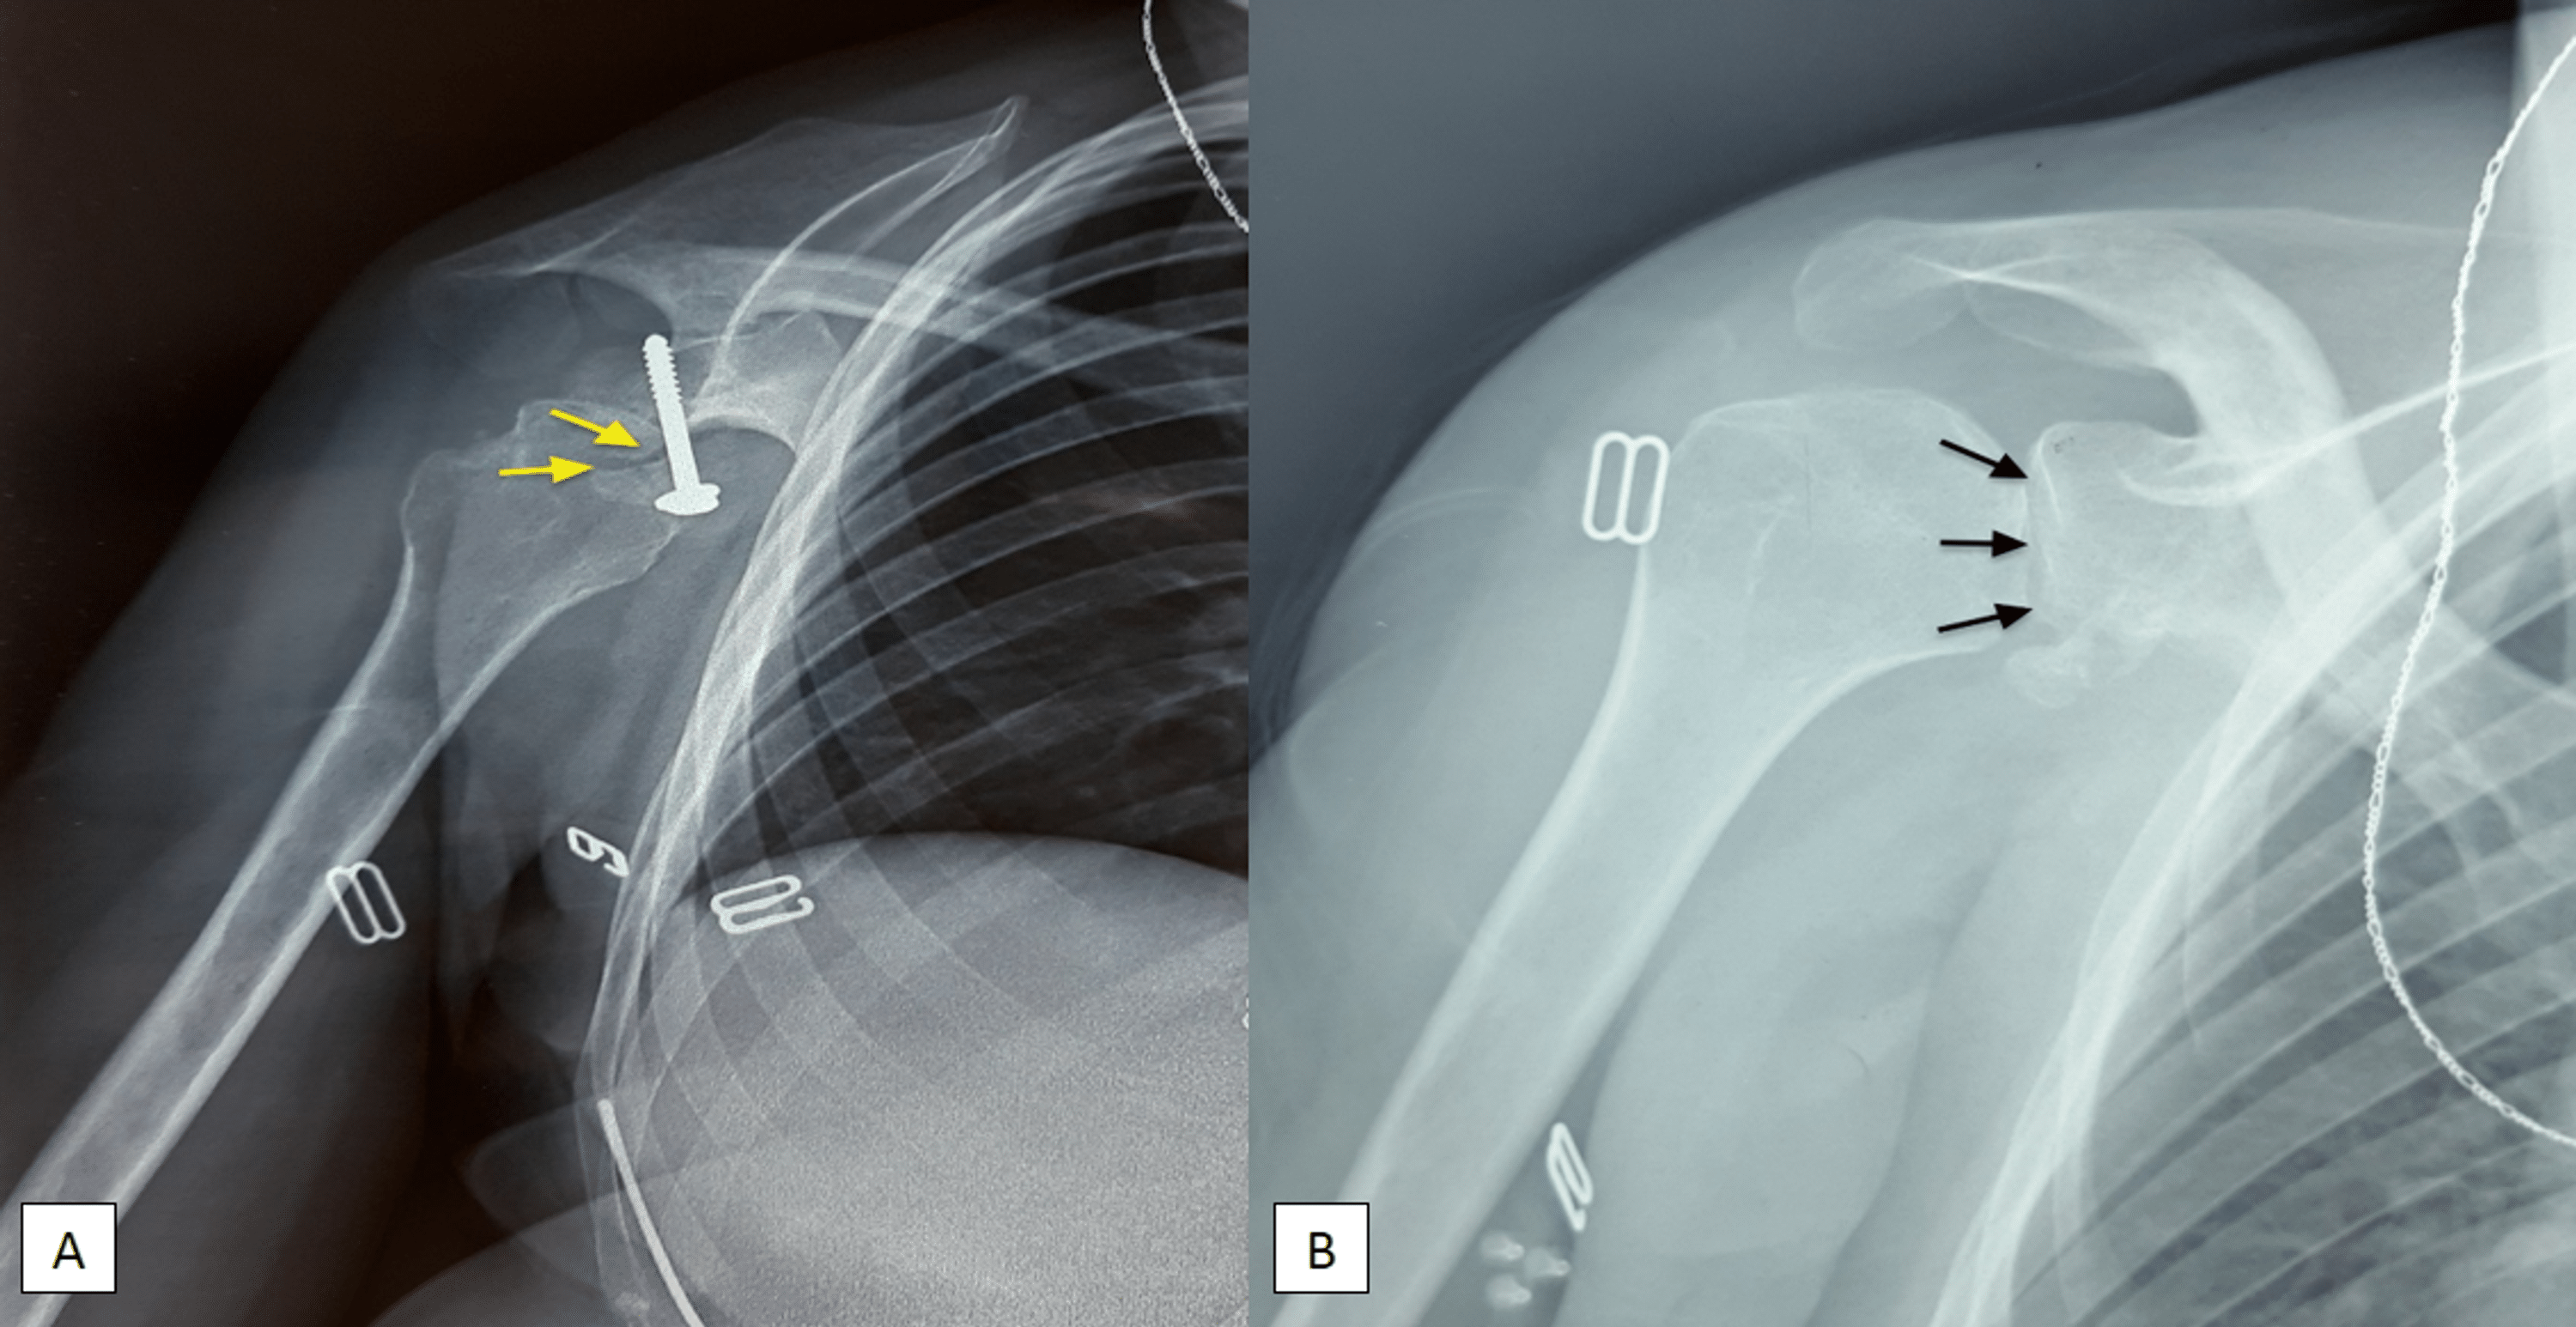

From www.cureus.com

Cureus Neglected Anterior Shoulder Dislocation Treated With Open Shoulder Replacement X Rays shoulder arthroplasty is the primary treatment of advanced glenohumeral arthritis once conservative measures fail, can restore function to. This article is chiefly limited to the routine radiographic evaluation of shoulder arthroplasties and guidelines to. They can show loss of the normal joint space between bones, flattening or irregularity in the shape of the bone, bone spurs, and loose pieces. Shoulder Replacement X Rays.